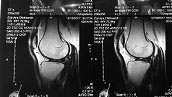

Вот фотографии коленного сустава.

Выражена гипотрофия четырехглавой мышцы